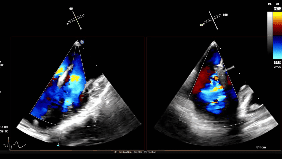

随后将可操控导引导管(SGC)及二尖瓣夹输送系统(CDS)送入左心房。仔细调整XTW二尖瓣夹的轨迹和方向后,进行首次夹合,超声提示仍存在少量二尖瓣反流,考虑为后侧瓣叶捕获不足所致,且侧边瓣叶仍存在明显脱垂。遂打开夹臂,在左心房内调整夹子位置,向后侧、外侧移动,以捕获更多后侧瓣叶,再次夹合,成功解决反流与脱垂问题,测得术后平均压差为4mmHg,手术圆满成功。

夹子释放后反流降至轻度

3D下组织桥稳定

3D下上彩

术后平均压差为4mmHg

值得关注的是,首次夹合后,TEE评估显示,患者二尖瓣反流已从术前的4+大幅改善,有效反流口面积显著缩小,初步达到目标。但潘湘斌教授团队秉持“精益求精”的诊疗理念,并未止步于此。团队通过超声精准测量发现,首次夹合后跨瓣压差偏高,恐无法置入第二枚夹子。在充分权衡调整夹子可能带来的瓣叶损伤风险与彻底修复带来的长期获益后,潘湘斌教授团队果断决定:在超声团队的精准配合下,打开瓣膜夹小心调整位置,向后叶方向移动,以捕获更多瓣叶。这一决策既体现了对患者长期健康的责任担当,也彰显了中国团队在纯超声引导TEER技术领域的深厚积累与精准把控,最终通过一次优化调整,圆满解决了反流与脱垂问题,实现了“微创化、精准化”的治疗目标,赢得了国际专家的高度认可。